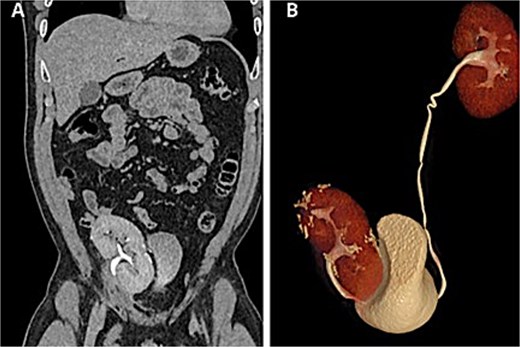

Renal function remained preserved at 1- and 6-month follow-up, with no evidence of recurrence (Fig. 4).

Postoperative CT scan. (A) Autotransplanted right kidney in the iliac fossa demonstrating symmetric contrast excretion and no residual lesions. (B) Normal calyceal morphology and nondilated pelvis; ureters with normal course and caliber.